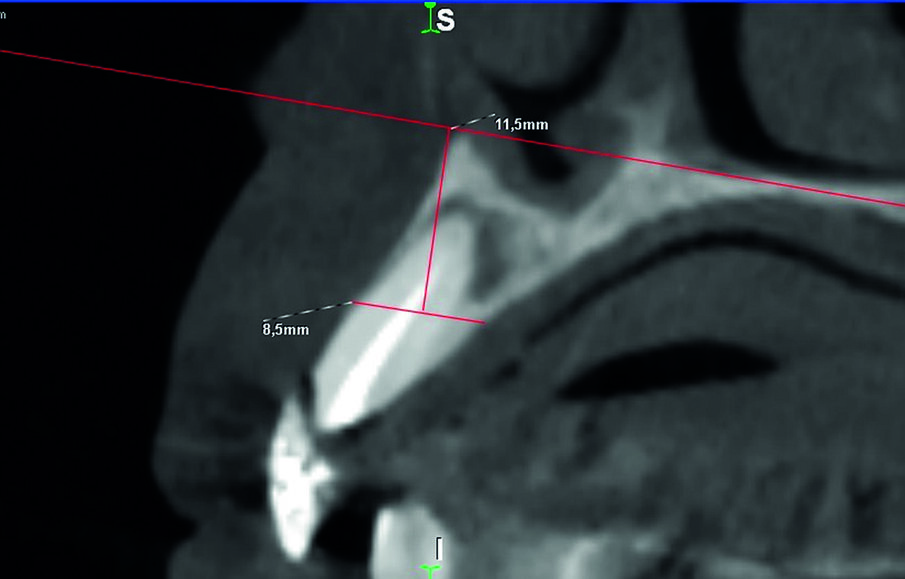

La paziente, di 54 anni, si è presentata al Centro Odontoiatrico Dentalnarco a Trezzano Sul Naviglio, Milano, Italia con tutti gli elementi residui del mascellare superiore compromessi (elementi 1.6, 1.4, 1.3, 1.2, 1,1 nel quadrante destro e 2.1 e 2.2 nel quadrante sinistro) (Fig. 1). A livello anamnestico, la paziente presentava un pregresso episodio di trombosi cerebrale ed era quindi in terapia anticoagulante con warfarin sodico (Coumadin, Bristol-Myers Squibb Srl, Roma, Italia); riguardo al valore INR (dall’inglese International Normalized Ratio), il range terapeutico impostato dai medici curanti era di 3. Avendo la paziente richiesto la massima riduzione possibile in termini di invasività dell’intervento, è stato dunque escluso in questa fase un intervento di grande rialzo di seno nel quadrante 2 e si è optato per un intervento di ridge preservation contestuale alle avulsioni. Per procedere alla corretta elaborazione del piano di trattamento, la paziente è stata sottoposta ad esame CBCT utilizzando un dispositivo ad alta risoluzione (Xmind TRIUM, ACTEON, Milano, Italia) con un FOV di 12 x 8 cm. Considerato il biotipo tissutale sottile della paziente, l’estensione dell’area crestale oggetto di trattamento e l’esiguo spessore della corticale vestibolare (Fig. 2), alla paziente è stato proposto un piano di trattamento che prevedeva l’avulsione di tutti gli elementi, l’innesto di un biomateriale a lento riassorbimento, il posizionamento di 5 impianti in un secondo tempo chirurgico e la riabilitazione definitiva attraverso una protesi fissa con chiavistelli liberamente rimovibile dal paziente. La paziente ha accettato il piano di trattamento e fornito il proprio consenso informato.

Fig. 2_Dettaglio CBCT (è mostrato l’elemento 1.2), esemplificativo dello spessore estremamente ridotto della corticale vestibolare della paziente, al limite della rilevabilità dell’esame diagnostico.

Figg. 6a, 6b_Misura degli spessori ossei. Viene mostrata a titolo esemplificativo la misura eseguita a livello dell’elemento 1.2. (A) sulla CBCT acquisita prima dell’estrazione si traccia una retta passante per la base del palato; successivamente si traccia una retta parallela alla prima, in posizione più coronale, dove si misura lo spessore osseo. (B) per misurare lo spessore osseo prima del posizionamento implantare si identifica la sezione corrispondente della seconda CBCT, sulla quale si riporta la stessa costruzione geometrica e si procede alla misura dello spessore osseo.